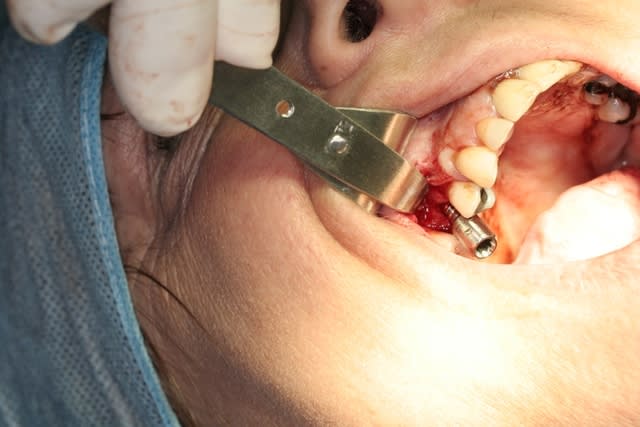

voilà un ptit cas de...disons 23 bis...car double agénésies des latérales...pas trop mal compensée naturellement secteur 1...mais persistance de la 63...à bout de souffle...

cette petite patiente ne veux pas d'ODF...mais ne veux pas rester sans dent...d'où cette intervention...avec la pose d'1 implant, avec expansion à l'aide de mon kit MIS... et mise en vitrine immédiate...

suite des photos...

désolé pour la surex des images...j'ai fait de mon mieux pour les rattraper...mais c'était une première pour mon assistante...